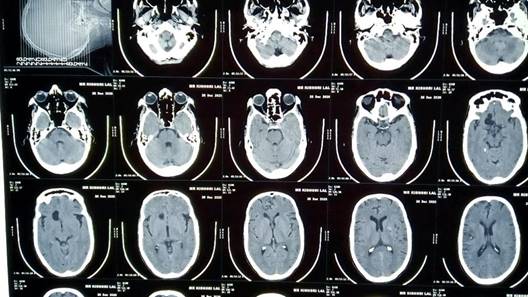

Figure 2: CT scan showing calcified lesion in frontal lobe of brain

Blood reports were hemoglobin 13 gm%, Neutrophils (N) 57%, Lymphocytes (L) 20%, Eosinophils (E) 14%, Monocytes (M) 1%, Erythrocyte Sedimentation Rate (ESR) 30 mm/first hour, Total Leukocyte Count (TLC) 7600 cells/mm3 and Random Blood Sugar (RBS) 110 mg%. His serology was negative. His urine routine microscopy was normal. A CT scan showed calcified lesion in frontal lobe (Figure 2).